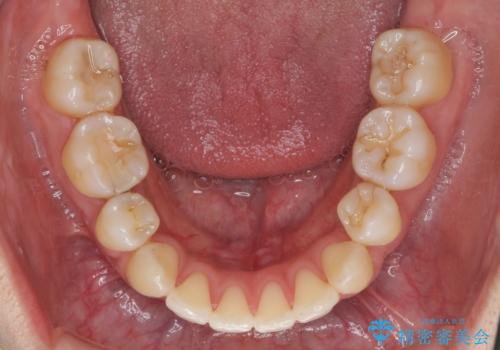

ガタつきと口元の改善 抜歯を伴うワイヤー矯正

前歯をしっかりと後方に引いたことで、唇は閉じやすくなり、仕上がりに満足いただくことができました。